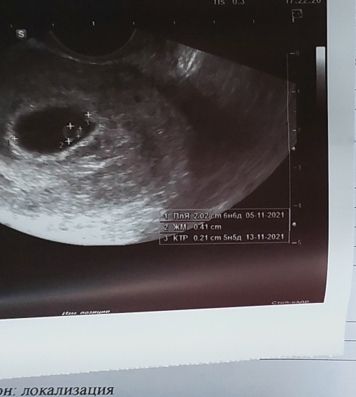

Татьяна в Благополучная беременность 4 года Какой срок в итоге?? 6.6 или 5.5 нед? От овуляции? Посмотрите еще 20 записей на эту тему Отменить Ответить Марина Ктр 0,21 см,т.е 2,1 мм это на срок 5+5 акушерских,а от овуляции 3+5 23.10.2021 Ответить Виктория Мустафина Срок смотрится по ктр 23.10.2021 Ответить Что надеть малышке на выписку? А на прогулку? Давление Чаты Беременных Выберите чат: Январята-2026 Февралята-2026 Мартята-2026 Апрелята-2026 Майчата-2026 Июнята-2026 Июлята-2026 Августята-2026